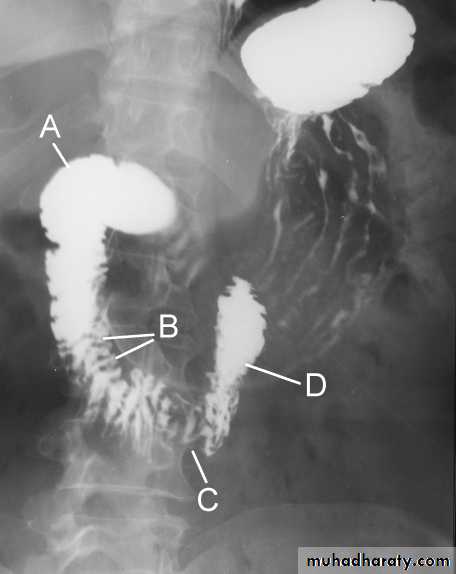

The Normal Anatomy of Stomach

1- Shape.2-Size.3-Site.4-Anatomical parts.5-Mucosal pattern.

Normal Anatomy of DuodenumA.Duodenal cap.

B.Duodenal loopHypertrophic pyloric stenosisCause:A. Congenital typeB. Adult type